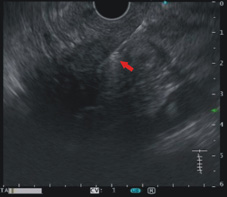

圖四、顯示利用超音波內視鏡導引針對病灶進行細針抽吸或是切片加以確診,以提供後續的治療方針(紅色箭頭)